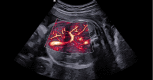

Diagnostic ultrasound (DUS) is, arguably, the most common technique used in obstetrical practice. From A mode, first described by Ian Donald for gynecology in the late 1950s, to B mode in the 1970s, real-time and gray-scale in the early 1980s, Doppler a little later, sophisticated color Doppler in the 1990s and three dimensional/four-dimensional ultrasound in the 2000s, DUS has not ceased to be closely associated with the practice of obstetrics. The latest innovation is the use of artificial intelligence which will, undoubtedly, take an increasing role in all aspects of our lives, including medicine and, specifically, obstetric ultrasound. In addition, in the future, new visualization methods may be developed, training methods expanded, and workflow and ergonomics improved.